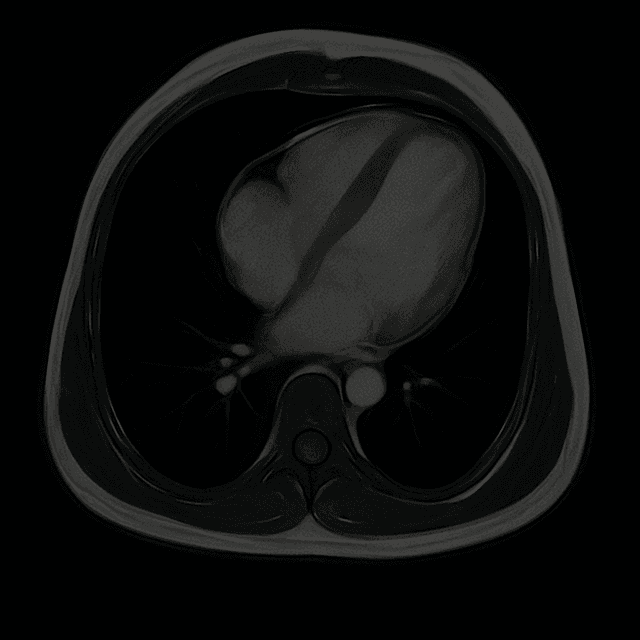

MRI

MRI - Detailed images of the heart's structure, function and tissue health to detect early health disease.

Full Body MRI

A detailed, radiation free scan of your entire body that detects tumors, organ issues, and structural abnormalities early before symptoms appear.